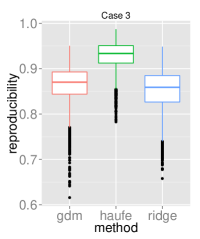

To assess the discriminative performance and reproducibility of the compared methods under varying confounding scenarios, we used the ADNI dataset. We simulated four distinct training scenarios in increasing potential for confounding effects: Case 1: AD + CN subjects, mean age balanced, Case 2: CN + AD, mean age balanced, Case 3: AD + CN, oldest ADs, youngest CNs, Case 4: CN + AD, oldest ADs, youngest CNs.

All models had their respective parameters () cross-validated in an inner fold before performing out-of-sample prediction on a left out test set consisting of equal numbers of AD and CN subjects with balanced mean age. Furthermore, the inner product of training model parameters was compared between folds to assess the reproducibility of models. Training and testing folds were shuffled 100 times to yield a distribution.

The prediction accuracies and the model reproducibility for the above cases are shown in figure 2. The results demonstrate that while GDM is not a purely discriminative model, its predictions outperformed ridge regression in all four cases. Regarding reproducibility, the Haufe et al. (2014) procedure yielded the most stable models since it yields a purely generative model. However, GDM was more reproducible than ridge regression.